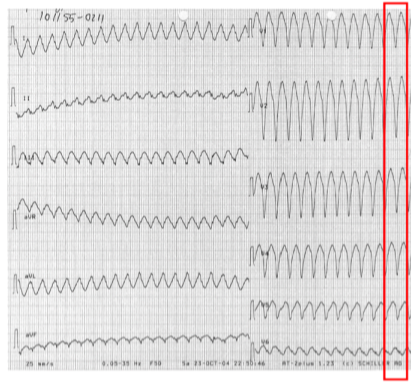

13

Q

Hvad ses på EKG’et?

A

monomorf VT

How well did you know this?